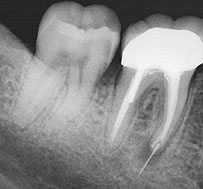

Breakage of endodontic files during treatment can result in serious complications and jeopardize the outcome of treatment. When using nickel-titanium (Ni-Ti) files, prevention of file breakage is complicated by the fact that these files rarely demonstrate visible evidence of cyclic fatigue and torsional stress and do not show wear before breakage.1 In the event that a file does break, removal can be difficult due to anatomical considerations, and the long-term prognosis of the tooth can become guarded.

An unfinished root canal will eventually cause many problems. The most common complication is that the tooth will begin to cause pain. There is also a risk that the tooth may fracture or cause a potentially dangerous swelling of the gum.

The greater the amount of uncleaned and unfilled canal space that remains after a root canal procedure, the greater failure rate. The challenge for clinicians is to decide to what point endodontic obturation should be directed in the given procedure. Cleaning, shaping and obturating less than the entire root canal space has the potential to or certainly could leave uncleaned and unfilled space, especially if the root is obturated to levels determined by arbitrary anatomic averages and not the true apical foramen.

Root canal overfills occur when a dentist is obturating (filling) a root canal. If the gutta percha(canal filling material) extrudes out the end of the root it is called an overfill. Sometimes, the gutta percha may have slipped through because it was not of sufficient diameter to bind at the apex. If a guttapercha that is too small is used, it can slip thru the tiny apical foramen (a hole at the tip of the root) and the resulting over fill may or may not form good seal . If the gutta percha does not adequately obturate (seal) the apex, then bacteria can repopulate any left over space. This bacterial colonization is most likely the actual cause of most endodontic failures associated with overfills.